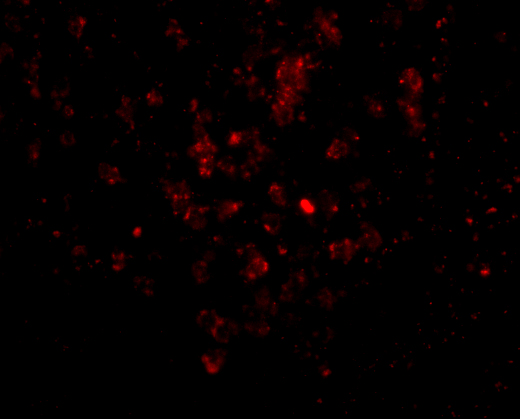

Facts about Interleukin-27 subunit beta.

Among its target cells are CD4 T-helper cells that can differentiate in type 1 effector cells (TH1), type 2 effector cells (TH2) and IL17 producing helper T-cells (TH17). It drives rapid clonal expansion of naive but not memory CD4 T-cells.